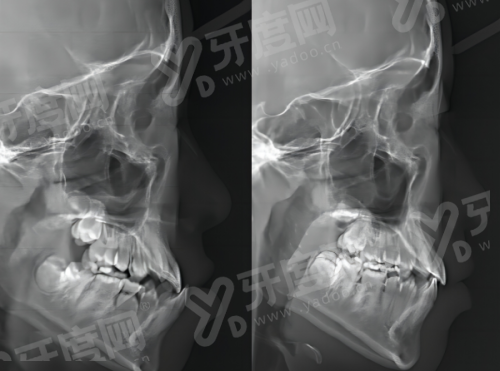

3、牙齿矫正方面,提供传统金属托槽、陶瓷托槽、隐形矫正等多种方式,医生会根据患者牙齿情况和美观需求制定个性化矫正方案,兼顾成效与舒适度。